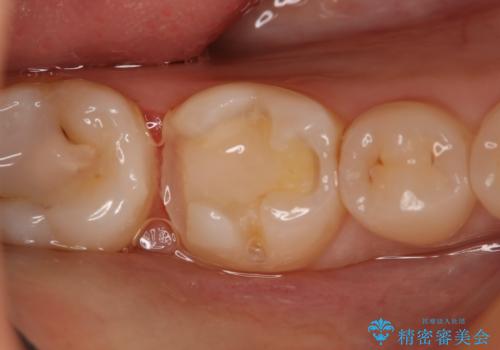

- 右下大臼歯の保険材料劣化に伴う虫歯の治療を希望された患者さまです。

審美性や精度の高い治療を希望されたので切削量や形態を考慮し、セラミックインレーでの治療を選択しました。

保険治療で使用される材料は劣化しやすく直下で虫歯が進行していることが多いです。

今回の患者さまは遠心部の虫歯が深かったのでCRで裏層した上で形成・印象を行いインレーセットを行っています。